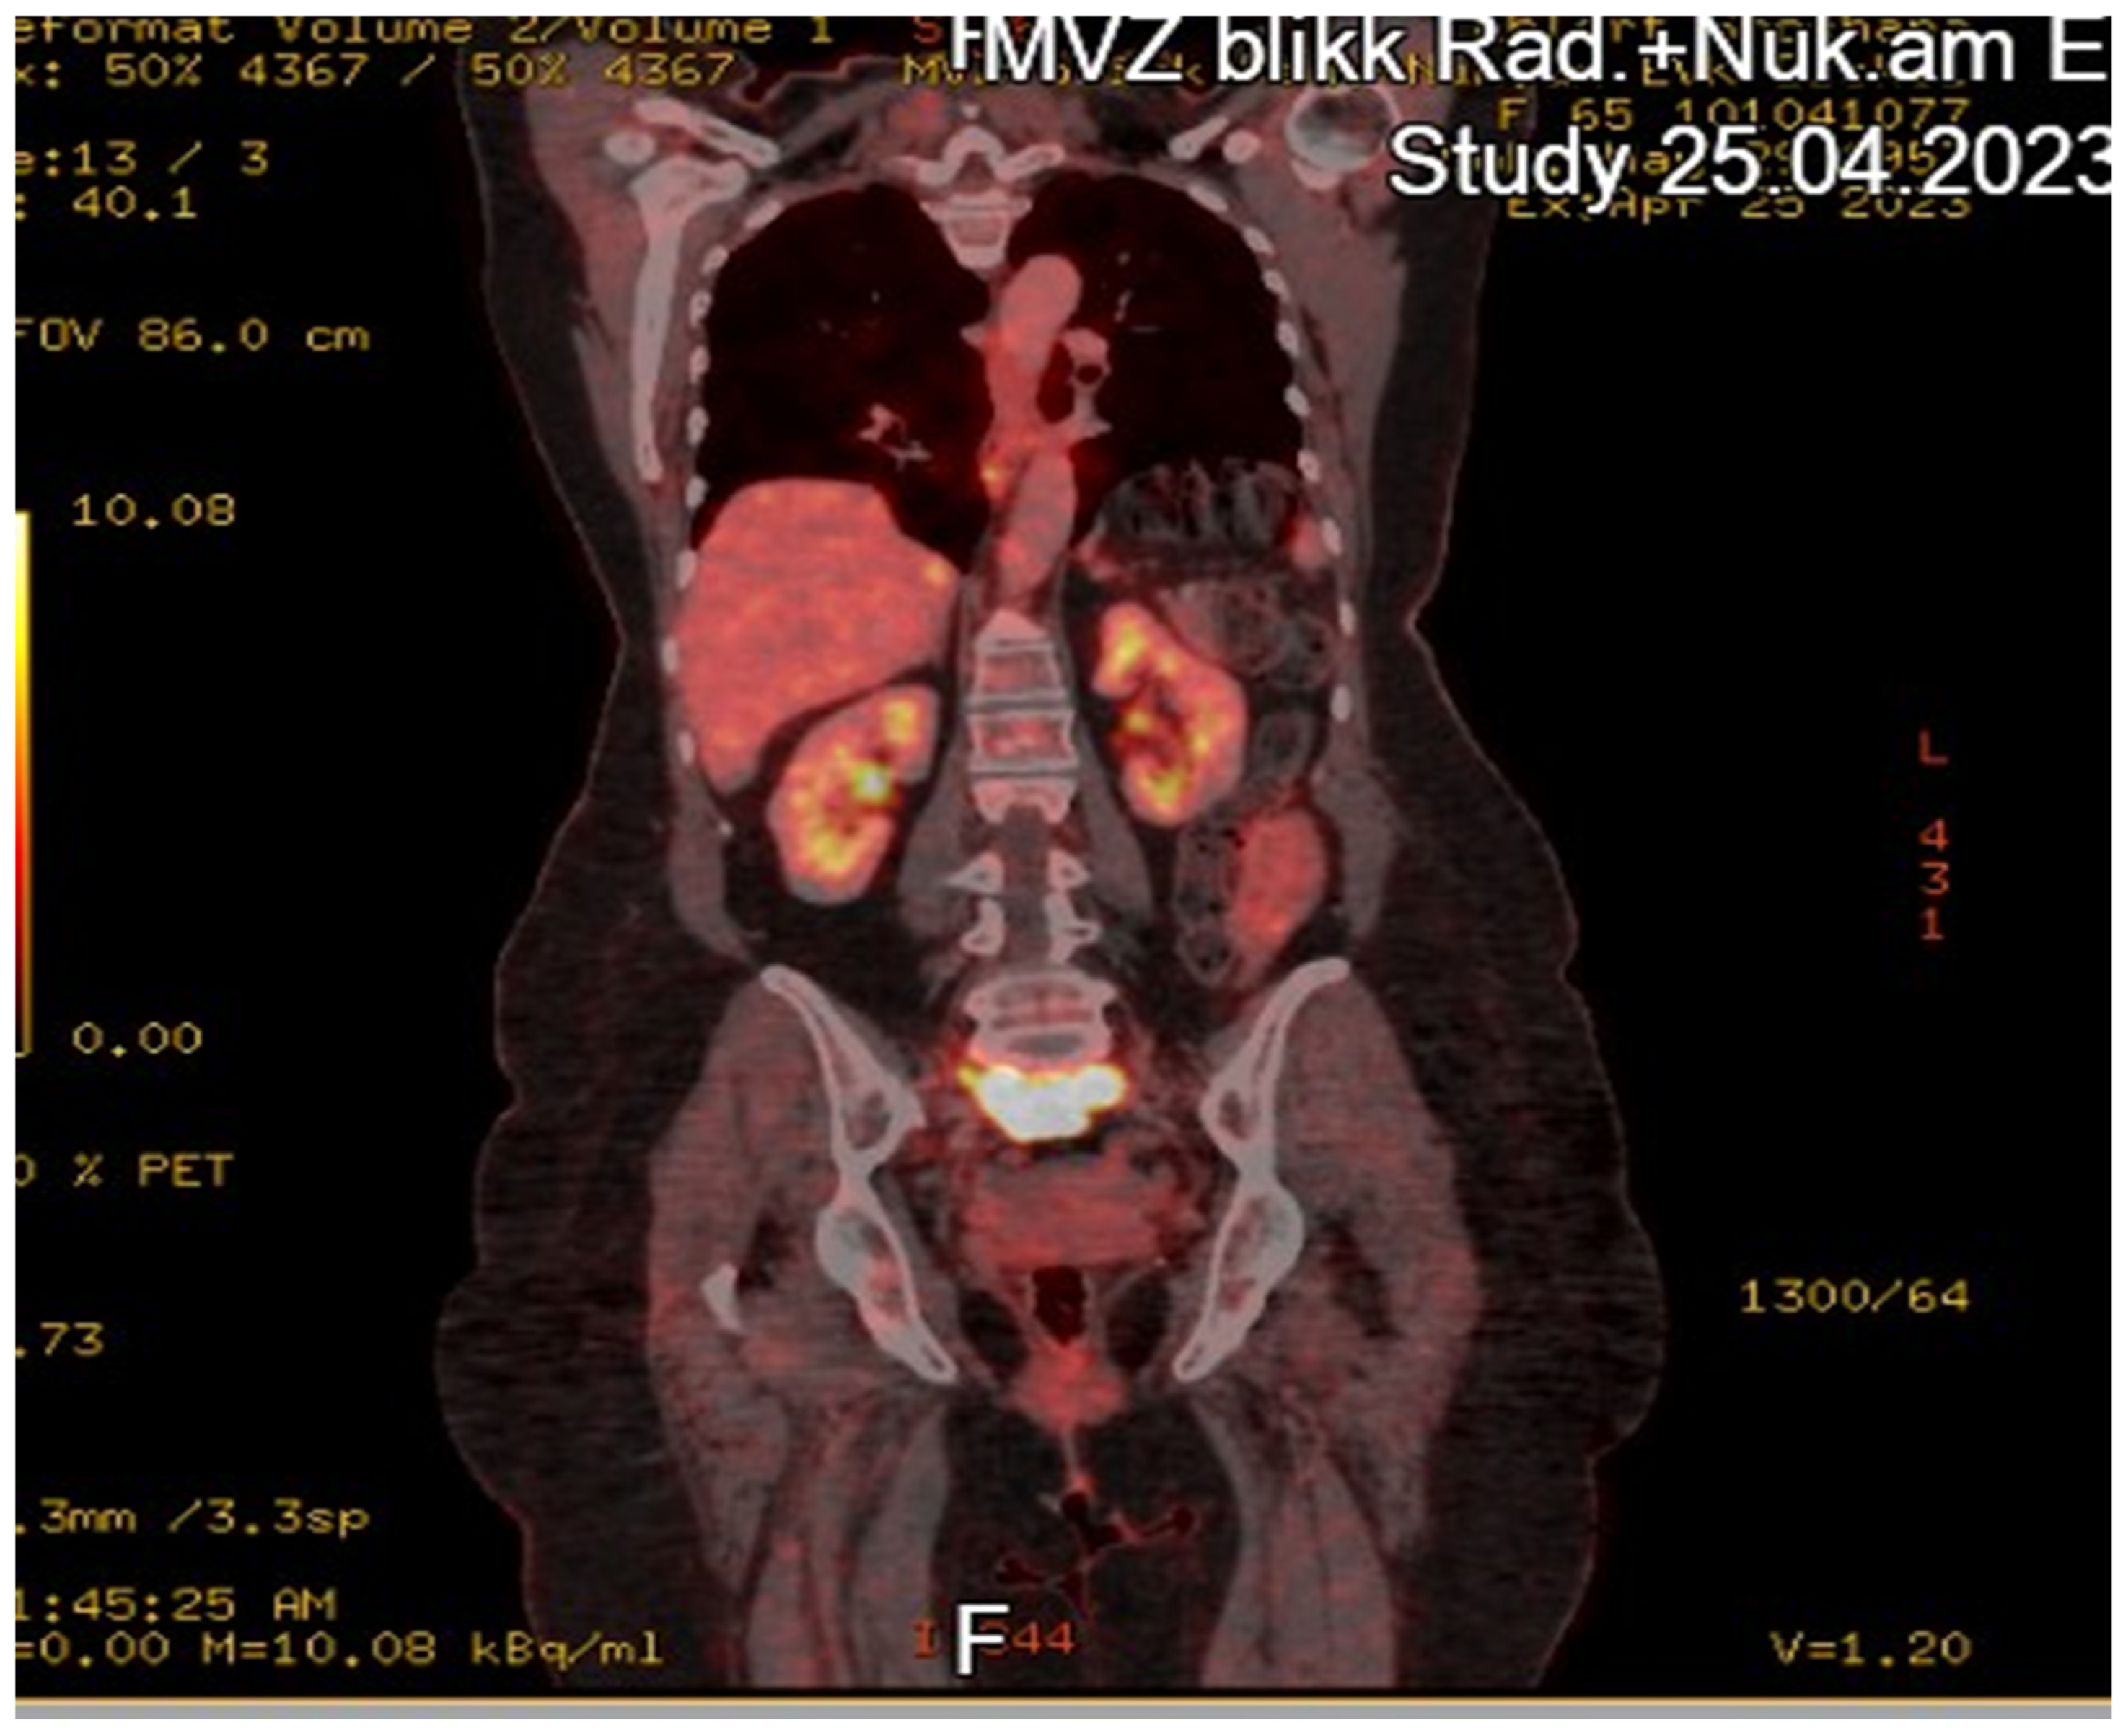

Case Report